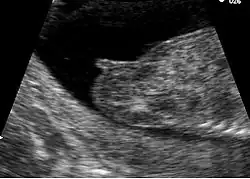

Genitalhöcker im Ultraschallbild in der 14. Schwangerschaftswoche